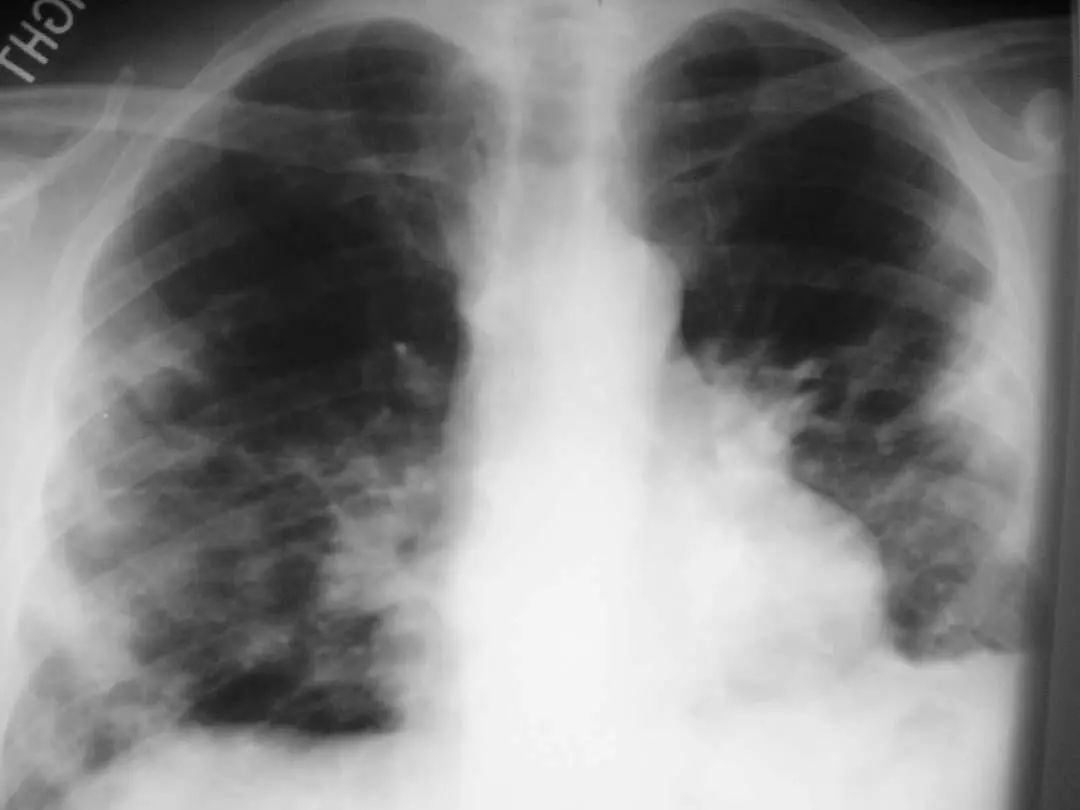

图1.5 40岁肺炎衣原体患者。胸片显示右上、中、下叶多灶性斑片状实变。